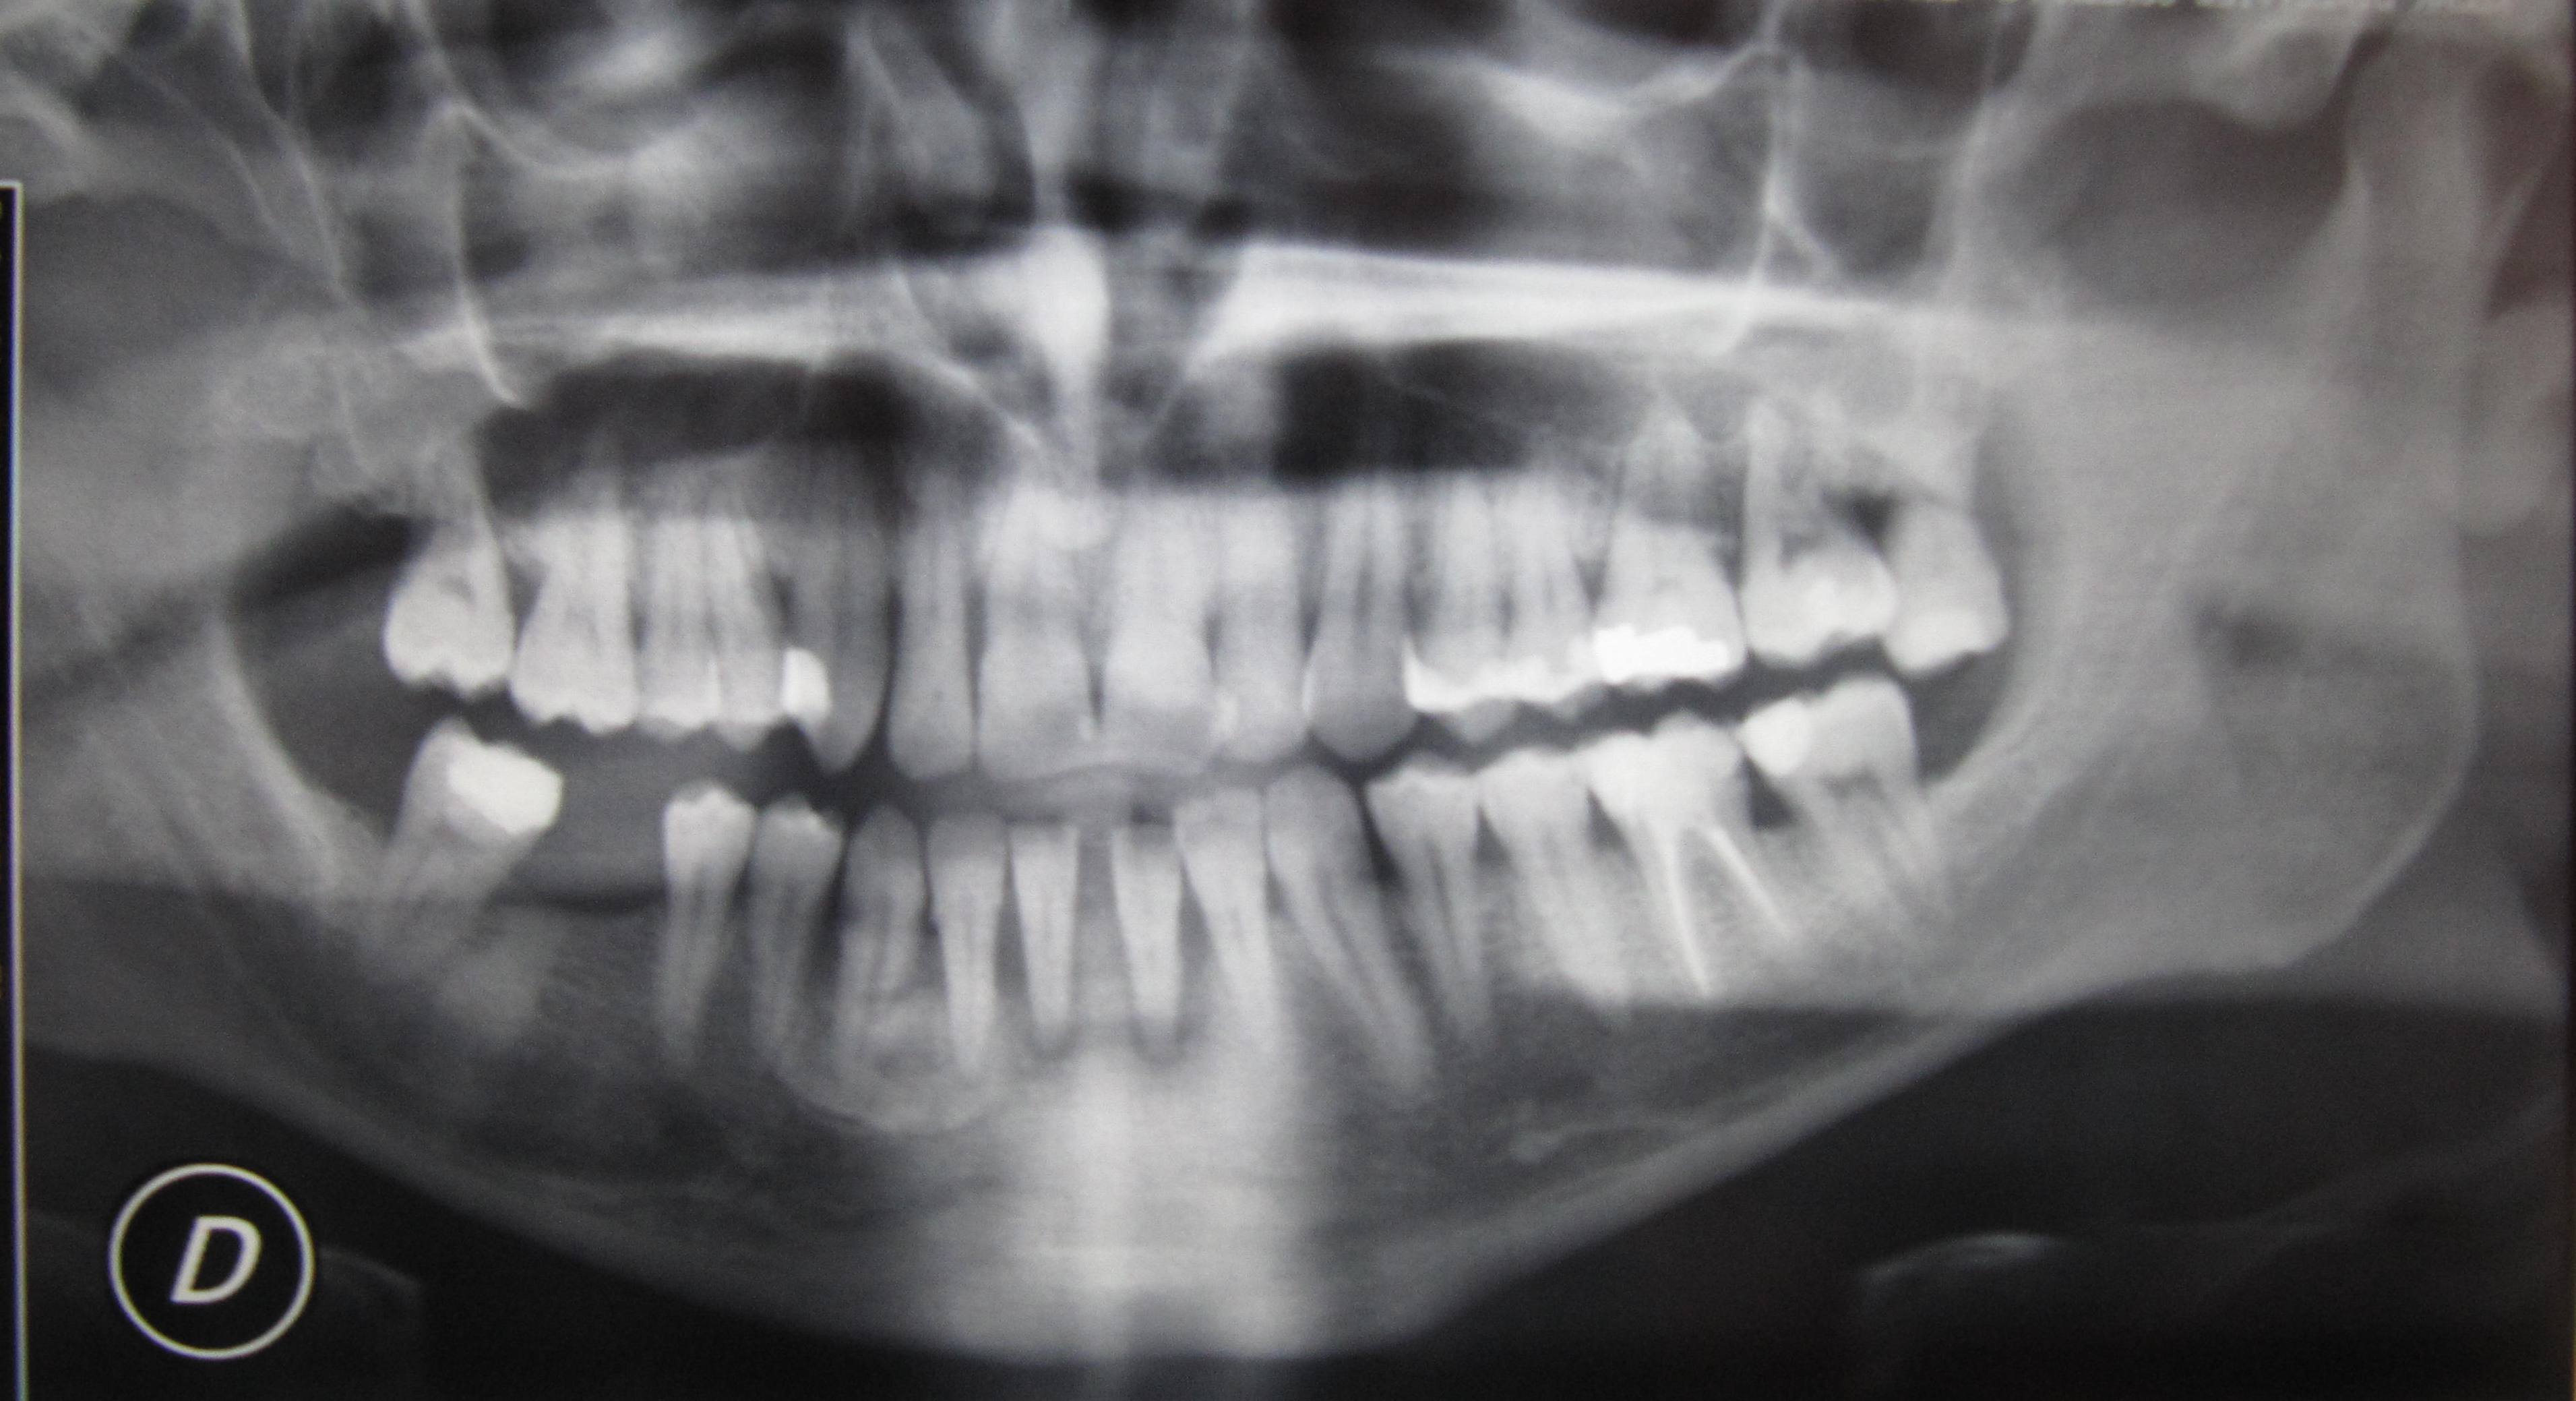

Sig. Antonello, per darle una seria risposta occorre una visita clinica con uno studio del caso. Dalla semplice OPT a distanza i due incisivi centrali inferiori sembrerebbero anche salvabili, ma ci mancano altri indici clinici per esprimere questa prognosi. Le consiglio, di seguire le indicazioni di chi ha prescritto l'OPT, senza interferire sul tipo di cura, in modo di avere un unico responsabile e senza compromessi; le ricordo che in regione emimandibolare destra mostra un’immagine che potrebbe essere compatibile con un elemento dentario ectopico, che sicuramente sarà discussa eventualmente confermata nelle prossime risposte dai miei colleghi, che possiedono esperienze radiologiche maggiori delle mie.

Gentile Paziente, la risposta alla sua domanda va considerata sotto un altro aspetto, perchè dalla radiografia sembrerebbe che lei presenti diversi problemi parodontali (piorrea) che vanno diagnosticati correttamente con un'accurata visita clinica, un sondaggio parodontale che si esegue su sei punti su ciascun dente e delle Rx endorali. Il suo problema principale non è la scelta tra ponte o impianti ma come poter salvare i denti che madre natura le ha donato! Inoltre vorrei farle valutare un altro aspetto altrettanto importante, diciamo "filosofico" per un corretto (ma per il momento inopportuno) approccio all'implantologia. La cosa in assoluto più importante che mi pare lei sottovaluti e che molto spesso passa sotto silenzio è: qual'è il grado di igiene orale domiciliare che riesce ad ottenere con spazzolino, filo e/o scovolino? Se lei è nella necessità (?) di estrarre alcuni denti è perchè o la malattia parodontale non è stata diagnosticata e trattata correttamente in passato oppure lei ha avuto un controllo della sua igiene orale non ottimale. Spero che le sia stato detto bene che anche e soprattutto la soluzione implantare richiede una igiene orale domiciliare molto accurata nel tempo, per evitare problemi spesso molto importanti come la perimplantite ("cugina" della parodontite), cioè un'infezione dei tessuti (osso, gengiva, legamento) che "sostengono" gli impianti. In questi casi, se la perimplantite non è prevenuta ed eventualmente trattata, si può andare incontro alla perdita degli impianti stessi esattamente come sta succedendo con i suoi denti! Inoltre spero le sia stato detto chiaramente che non basta fidarsi di vaghe promesse da parte del paziente (sì,sì, pulirò bene i denti...) ma è buona norma effettuare, negli anni seguenti, anche richiami di igiene orale professionale in studio, per controllare bene la salute dei tessuti e quindi salvaguardare il suo "investimento"! Quindi capisce che la discriminante per scegliere una soluzione o l'altra non è di natura "tecnica" ma se lei riuscirà prima di ogni altra cosa ad avere un'igiene orale ottimale per tutta la vita. Cordialmente

Caro Signor Antonello, voglio proprio sperare che queste considerazioni che ha esternato, le abbia fatte lei e non il suo Dentista! Si preoccupa, in parole povere, della "fine della storia", quando non sa neanche come iniziarla e proseguirla! Anche se la OPT postata non è certo l'ideale per una diagnosi Parodontale ed Odontoiatrica e anche se questa diagnosi non è possibile farla ad occhio, via web! Data la mia esperienza di ormai 36 anni, le posso dire che ha dei difetti ossei evidenti, sembrerebbe a più pareti complesse e quindi con tasche parodontali, in tutta la bocca ed in particolare sui frontali inferiori dove lei parla di protesi o impianto, che sono espressione di una parodontite DNDD. Ovvio che questo andrà confermato clinicamente con una Visita Parodontale, sondaggio delle tasche e valutazione della mobilità dentale e tanto altro e preparazione iniziale Parodontale con Pulizia dei Denti Professionale e curettage e scaling e Root planing e modelli di studio e serie complete di Rx Endorali parodontali e valutazione Gnatologica e conservativa dei denti e seconda visita parodontale di rivalutazione per avere la reale entità dei danni dopo aver rimosso il tessuto di granulazione delle tasche con il curettage e scaling. Parlo di conservativa perchè gli incisivi centrali in particolare hanno due difetti ossei verticali distali veramente profondi, sembrerebbe sui 10-12 mm. ed osteolisi periapicali per cui potrebbero essere in necrosi e quindi vivi e non vitali con granulomi e osteolisi periradicolari endoparodontali che implicherebbero la loro cura endodontica, dopo diagnosi della loro vitalità con stimoli termici etc, e quindi conservativa e eventuale immobilizzazione parodontale preintervento chirurgico parodontale! Se quello che ha detto non fosse "farina del suo sacco" ma un dubbio del Dentista, cambi Dentista perchè non capisce evidentemente le sue innumerevoli patologie per di più manifeste alla giovane età di 35 anni! Sappia che una tasca parodontale, quando si forma per distacco del suo attacco al ente, va avanti con una velocità di 1/2 mm l'anno! Quindi per esempio se avesse anche solo tasche di 4-5 mm. ci vorrebbero 8-10 anni perchè si siano potute firmare e quindi chi l'avesse vista odobtoiatricamente per qualsiasi motivo, non avrebbe fatto Diagnosi di Parodontite! Ovvio che dico questo ma la prego di recepirlo con le dovute precauzioni perchè non la vedo clinicamente ma. ripeto, è veramente molto probabile purtroppo che lei si trovi in queste situazioni patologiche! Le tasche possono essere anche maggiori, me le aspetterei sui 6-7 mm almeno perchè vi sono difetti ossei che in tasche minori non ci sarebbero! Lei ha bisogno di una visita Parodontale, preparazione parodontale e seconda visita di rivalutazione completa parodontale, odontoiatrica e gnatologica, ripeto per avere una diagnosi che deve essere completata dalla valutazione del frenulo interincisivo a livello del diastema, della quantità di gengiva aderente presente e della adeguatezza anatomica dei fornici e pianificare una terapia parodontale adeguata! Altroché impianto!!! Le lascio un Poster di Chirurgia Parodontale per la terapia di difetto ossei, la invito a leggere sul mio profilo,"Parodontite (nozioni di etiopatogenesi, clinica, diagnosi)" e "Terapia chirurgica della parodontite La Terapia Parodontale, consiste essenzialmente nel ricostruire chirurgicamente ciò che la malattia parodontale ha distrutto" e "La tasca parodontale.... questa sconosciuta!" e "VISITA PARODONTALE". Bisogna fare anche accurata Diagnosi Deffierenziale Sistemica oltre che Odontostomatognatica per valutare clinicamente l'intero stato di salute del suo organismo se fosse confermata una Parodontite e Diagnosticata esattamente quale, perchè è troppo giovane per avere una parodontite con difetti ossei! Quindi il Dentista o Parodontologo deve essere un eccellente Parodontologo che sappia valutare il Parodonto senza estrapolarlo dal contesto clinico generale e sistemico!Cordialmente Gustavo Petti, Parodontologia, Implantologia, Gnatologia, Endodontia e Riabilitazione Orale Completa in Casi Clinici Complessi ed Ortodonzia e Pedodonzia la figlia Claudia Petti, in Cagliari

Gentile Antonello, più volte è stato detto che la panoramica non è assolutamente sufficiente per stilare una diagnosi corretta ed un piano terapeutico adeguato ma è assolutamente necessario procedere ad una visita accurata con test di vitalità, sondaggio parodontale e radiografia endorale. Comunque, per risponderle, dalla radiografia sembrerebbero esserci dei seri problemi parodontali evidentemente mai affrontati e risolti. Pertanto le consiglio di rimuovere questi problemi prima di affrontare un percorso protesico con ponti o impianti. Cordialmente

Gentile paziente, nel caso i suoi denti incisivi centrali, sicuramente affetti da parodontopatia e mobilità, dovessero essere avulsi, le consiglio vivamente di mettere degli impianti, previa Tc cone beam 3d, dove verrà visualizzata sia la quantità ossea che la relativa qualità (densità residua presente). Meglio evitare di fare un ponte, andrebbe a rovinare biologicamente anche altri 2 denti vicini, che appaiono in buono stato apparentemente dalla Opt. che ci ha presentato. Per il diastema non si preoccupi, quello si potrà risolvere dal punto di vista estetico protesicamente realizzabile. Cordiali saluti Dr. Tommaso Giancane

Personalmente opterei per gli impianti, ma solo dopo aver ristabilito un'adeguata salute orale complessiva, con riequilibrio occlusale e guarigione dalla diffusa parodopatia. Altrimenti andrà incontro ad un fallimento terapeutico. Cordiali saluti.

Radici corte e poco osso di non eccelsa qualità. Controindicazioni relative per tutti e due i tipi di lavorazione propostole. Il suo caso è facile sulla carta ma di una certa difficoltà nel mondo reale. Si affidi alle cure di un professionista coi fiocchi, oppure l'insuccesso è dietro l'angolo. Si faccia bene chiarezza su vantaggi e svantaggi di entrambe le lavorazioni. Non si elimineranno i rischi, ma si sceglierà in maniera consapevole. Cordiali saluti.